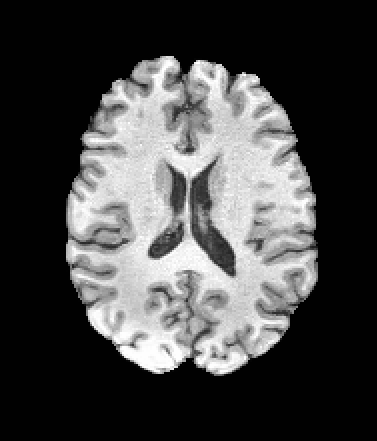

A distinctive strength of MetaVoxel is its ability to perform flexible zero-shot inference for a broad spectrum of tasks with arbitrary subsets of inputs. To enable this, we reinterpret the RePaint strategy described in Section 2: just as RePaint performs conditional image generation by specifying a binary mask that marks which pixels are fixed, we can further designate any subset of MetaVoxel’s variables as “known” conditions. At each denoising step, these known variables are overwritten with their re-noised values, ensuring that they remain fixed throughout the sampling trajectory, while the remaining variables evolve according to the learned reverse process. This keeps the synthesized variables consistent with the conditioning, analogous to how RePaint produces inpainted regions consistent with the known region. Although MetaVoxel learns the joint distribution , different downstream tasks can be realized simply by choosing which variables to fix during sampling. Image inpainting is achieved by fixing pixel regions of the image variable***see examples in Appendix (Figure B.2); conditional image generation by fixing variables such as age or sex; regression tasks (e.g., age estimation) by fixing any combination of image and sex; and classification tasks (e.g., sex prediction) by fixing any combination of image and age. As more variables are included in the joint model, the range of possible zero-shot tasks naturally expands. For example, when multiple imaging modalities are present, fixing one modality and sampling the other enables image-to-image translation.

| Input | Inpainting with Left Half of the Image Fixed | ||||

|---|---|---|---|---|---|

![]() |

|